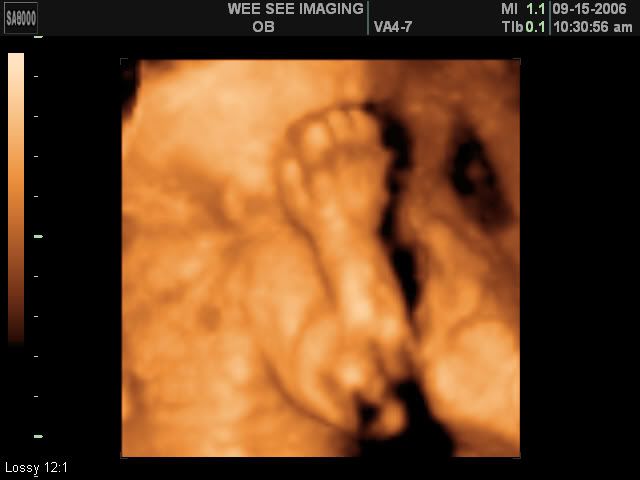

Victoria Rose Kelly

Date Due: December 15, 2006